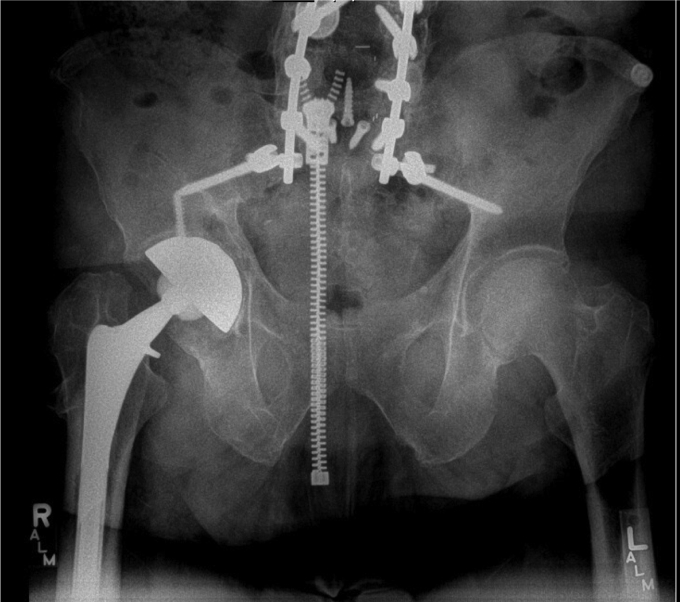

In September of 2019, now 67 years old, the patient presented back with increasing right hip pain. He reported 3-year history of intermittent dull hip pain localized to the groin causing him to regress and ambulate using a cane. In addition, he complained of progressive squeaking coming from his right hip especially as he transitioned from a seated to a standing position. He further felt like the implant had started shifting inside and developed a reproducible, audible clunk. On physical examination, he had a moderate limp and slightly decreased abductor strength compared with his contralateral side, but a true trendelenburg gait was not appreciated. Review of his radiographs illustrated progressive radiolucency around the acetabular component compared with early postoperative images (Fig. 2). A Technetium 99-m bone scan showed a right hip prosthesis with mild periprosthetic uptake adjacent to the right greater trochanter corresponding to a 4.7 × 6.0-cm fluid collection previously seen on a CT scan ordered by his primary care physician (Fig. 3). Physical examination revealed full extension with flexion of the hip to 95°. He was able to externally rotate to 35° and internally rotate to 10° in a seated position. The previously mentioned clunk was appreciated in the office as he moved his hip from flexion to extension while getting up from a chair.

Figure 2.

Prerevision AP pelvis illustrating periacetabular radiolucency without any other obvious signs of malalignment or positioning.